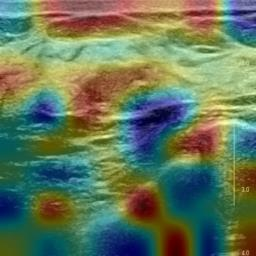

Ultrasonography is an important routine examination for breast cancer diagnosis, due to its non-invasive, radiation-free and low-cost properties. However, it is still not the first-line screening test for breast cancer due to its inherent limitations. It would be a tremendous success if we can precisely diagnose breast cancer by breast ultrasound images (BUS). Many learning-based computer-aided diagnostic methods have been proposed to achieve breast cancer diagnosis/lesion classification. However, most of them require a pre-define ROI and then classify the lesion inside the ROI. Conventional classification backbones, such as VGG16 and ResNet50, can achieve promising classification results with no ROI requirement. But these models lack interpretability, thus restricting their use in clinical practice. In this study, we propose a novel ROI-free model for breast cancer diagnosis in ultrasound images with interpretable feature representations. We leverage the anatomical prior knowledge that malignant and benign tumors have different spatial relationships between different tissue layers, and propose a HoVer-Transformer to formulate this prior knowledge. The proposed HoVer-Trans block extracts the inter- and intra-layer spatial information horizontally and vertically. We conduct and release an open dataset GDPH&GYFYY for breast cancer diagnosis in BUS. The proposed model is evaluated in three datasets by comparing with four CNN-based models and two vision transformer models via a five-fold cross validation. It achieves state-of-the-art classification performance with the best model interpretability.

翻译:超声波分析是乳腺癌诊断的一个重要常规检查,原因是其非侵入性、无辐射和低成本的特性。然而,由于其内在局限性,它仍不是乳腺癌的第一线筛选测试。如果我们能够精确地通过乳房超声图像诊断乳腺癌(BUS),它将是一个巨大的成功。我们提出了许多基于学习的计算机辅助诊断方法,以实现乳腺癌诊断/感官分类。然而,其中多数方法需要事先确定性能模型,然后对ROI内部的跨值进行分类。常规分类支柱,如VGG16和ResNet50等,可以在没有ROI要求的情况下实现有希望的分类结果。但是这些模型缺乏可解释性,从而限制了其在临床实践中的使用。在本研究中,我们提出了一个新的无乳腺癌诊断模型,在超声波图像中进行解释性特征描述。我们利用了先前的解剖学学学知识,即恶性肿瘤和良性肿瘤模型在不同组织层之间有着不同的空间关系,并提议采用状态解析法来编制这一先前的知识。拟议中的HOVer-Trans-Trading-Tradef-trainal Ex-deal-dealal-deal-deal-deal-degraphal-deal-deal-deal-deal-deal-deal disal disal-dal-dal-dal-dal-dal-deal-deal-dal-deal-deal-deal-dal-dal-dal-dal-dal-dal-dal-dal-dal-dal-dal-dal-dal-dal-I-dal-Iversal-dal-Ial-d-d-I-d-d-I-I-I-I-I-I-I-I-I-I-I-I-I-I-I-I-I-I-I-I-I-I-I-I-I-Ial-I-Ial-Ial-I-I-I-I-I-I-I-I-I-I-I-I-I-I-I-I-I-I-I-I-I-I-I-I-I-I-I-I-I-I-I-I-